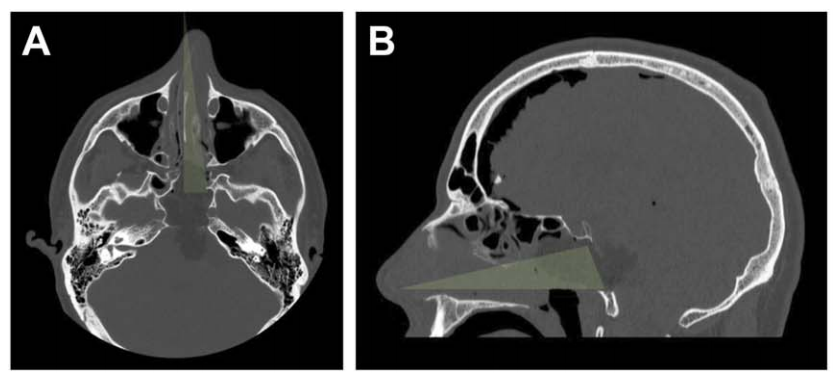

最终,在INC福教授制定的个体化手术策略下,从术前栓塞、入路选择到手术实施,无需开颅操作,仅通过右侧单鼻孔入路,使用内镜技术成功全切肿瘤。术后脑干复位良好,未出现脑脊液漏及新发神经功能障碍,术后第一天患者可下床活动,术后一周顺利出院。关闭术腔时,采用腹部脂肪填塞硬膜内腔及蝶窦,并缝合鼻黏膜,表面覆盖硅胶片保持湿润;硅胶支架留置4周后取出。

A、B:术后CT轴位及矢状位显示,绿色标示单鼻孔入路,鼻腔完整性得以保持;鼻中隔、上颌窦、后组筛窦及左侧蝶窦间隔均完整。